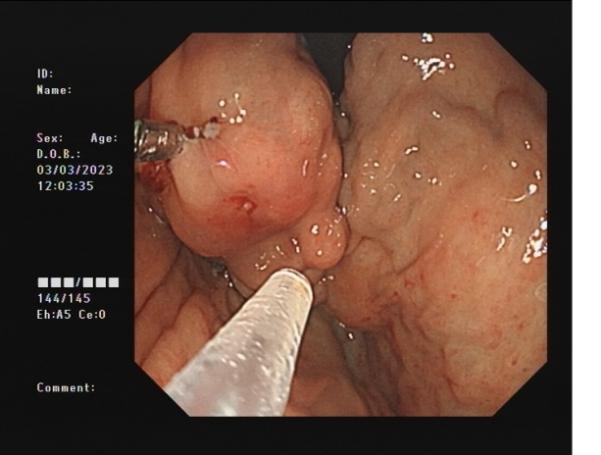

0d0b80a96701483cbcbf8b67351feac3.Jpeg8f7177645651428ca3a0f3c87dfd559d.Jpeg

直腸側向發育性腫瘤      內鏡下黏膜下剝離術后創面

內鏡下黏膜剝離術(ESD):治療巨大平坦息肉,早期癌及癌前病變,黏膜下腫瘤等。